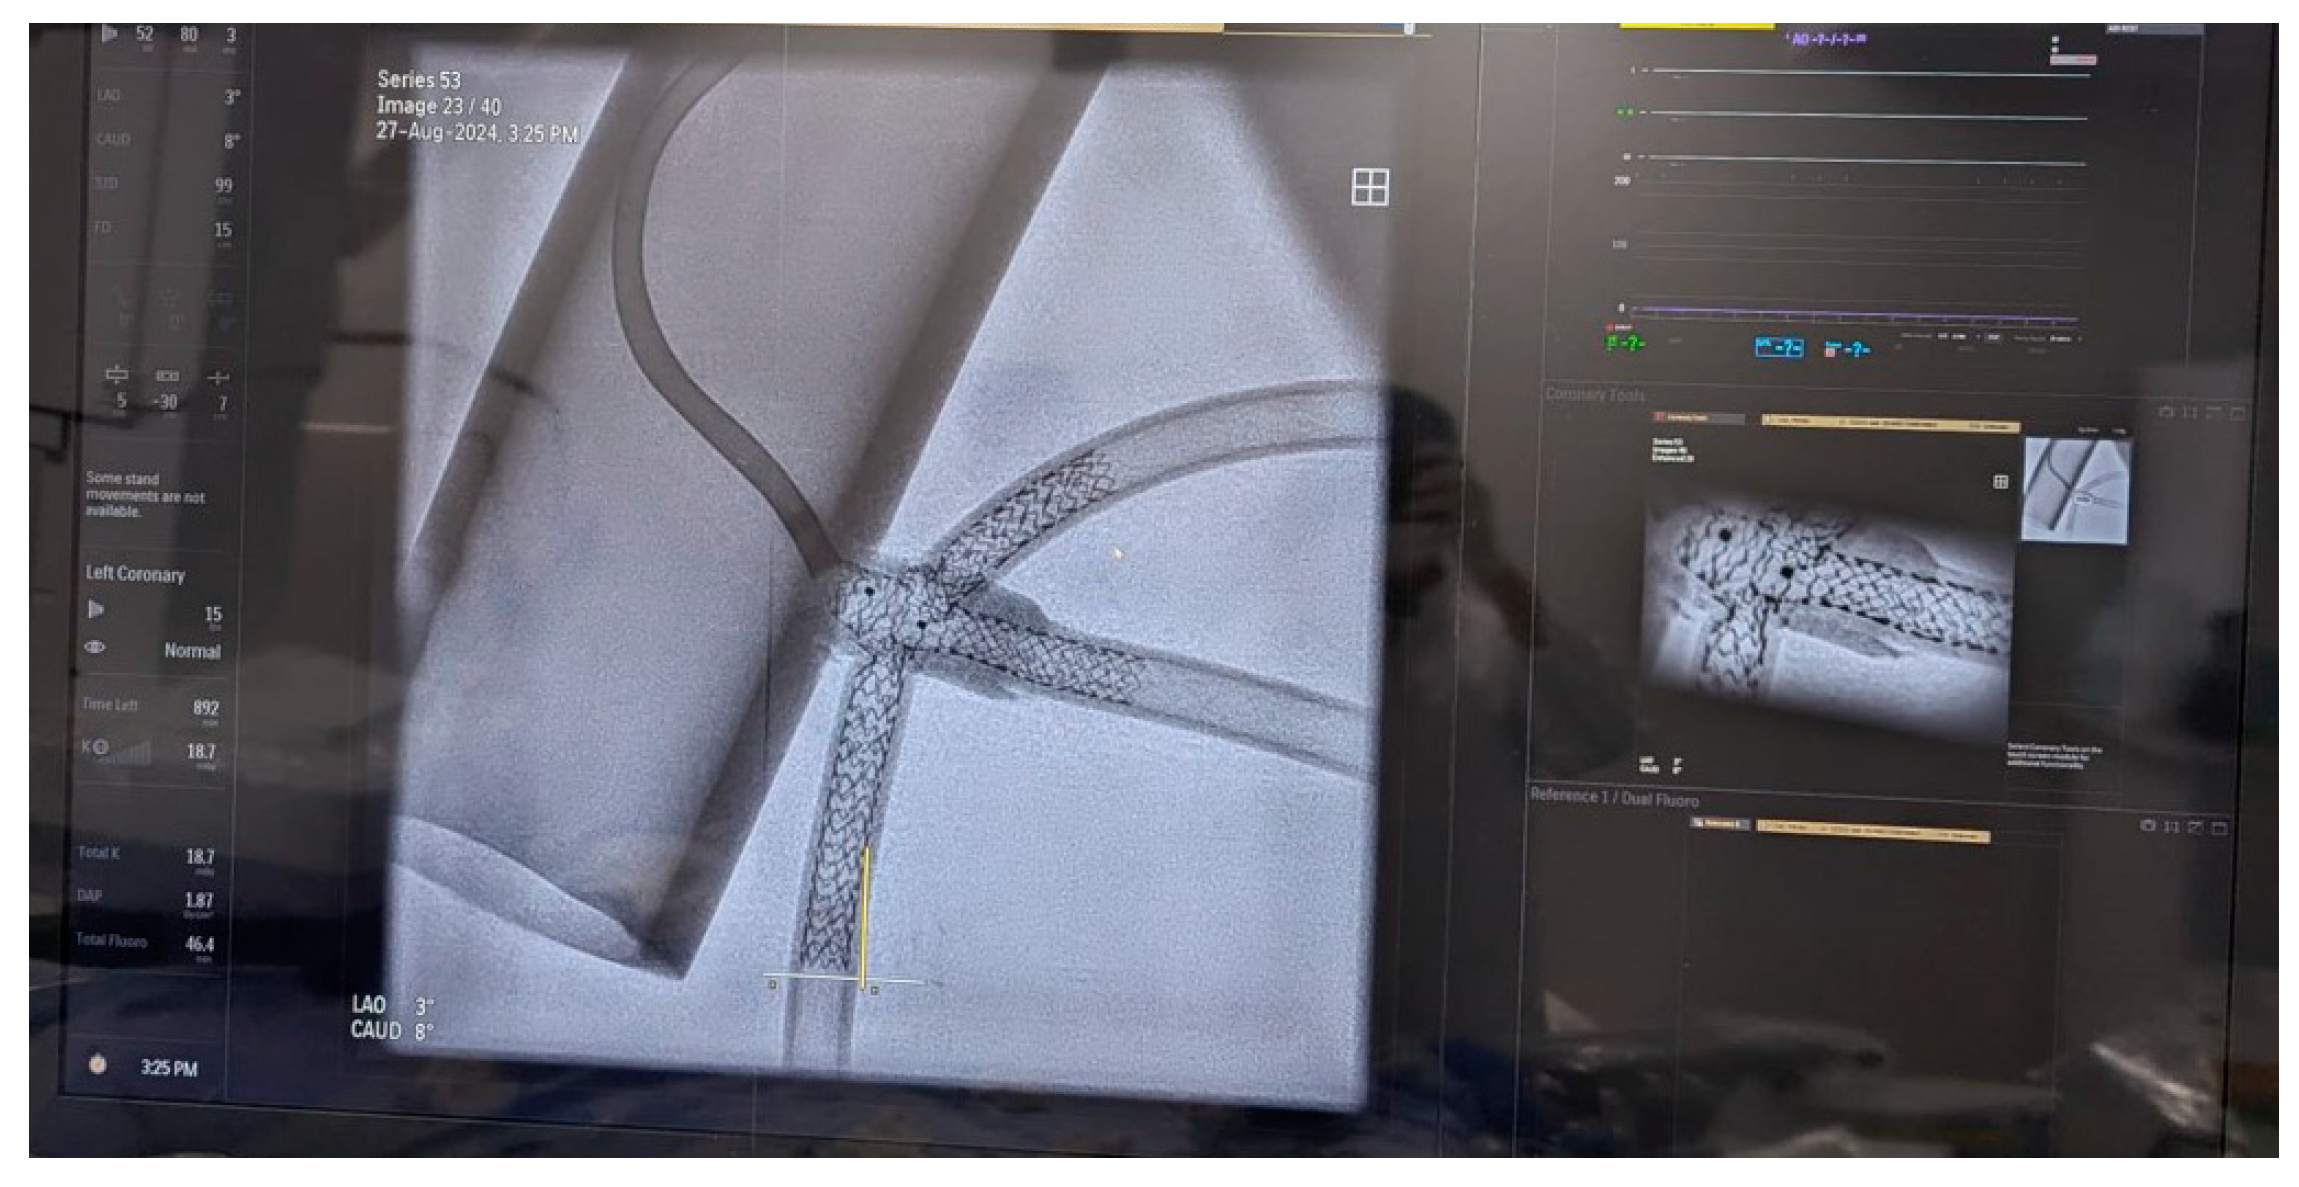

In preparation for the in vivo intervention, we planned the steps and performed an in vitro procedure to see what happens to the crushed stents, the amount of overlay stent struts at the carinas level, and the main vessel stent deformation related to the post-dilation (Figure 11, Figure 12 and Figure 13).

Figure 11.

In vitro procedure.

Figure 12.

In vitro procedure—model close-up.

Figure 13.

In vitro procedureunder X-rays.